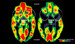

Estas ratios podrían sonar medio bien, comparándolas con las ratios de las escuelas infantiles actuales. Sin embargo, comparándolas con el papel de un padre y una madre, es como si una madre tuviera diez hijos de un mes que cuidar día y noche, y otra madre tuviera 20 hijos de 3 años. Esto hacía que la mayoría de bebés llegaran a pasar hasta 20 horas al día en sus cunas. Estos niños fueron adoptados por familias de Reino Unido y EE.UU., y algunos investigadores quisieron estudiarles incluso cuando ya llevaban mucho tiempo con sus nuevas familias. El resultado, que podéis ver en la imagen, sirvió para conocer cómo puede afectar el estilo de crianza de los padres en el desarrollo cerebral de los hijos.

A la hora de comparar los escáneres cerebrales observaron que estos niños, que habían recibido los cuidados básicos en el orfanato, con comida, cobijo, una cuna y ropa limpia, pero que carecieron del cariño y la atención de unos padres, tenían zonas inactivas en muchas partes del cerebro (en negro las zonas no activas, en rojo las más activas). Centrándose en las zonas inactivas, vieron que eran sobre todo los lóbulos temporales, donde se procesan y regulan las emociones. Al no haberse activado como en los otros niños, la lógica decía que estos niños podían tener una menor capacidad social y emocional, y como vieron en las pruebas, esto se confirmaba.